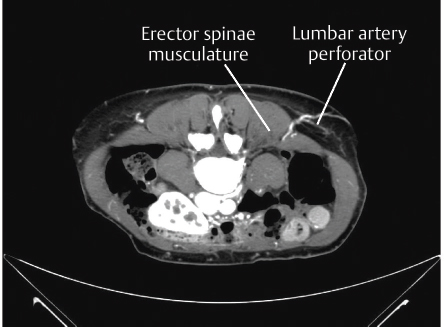

Location: Perforators from the upper three lumbar vertebral bodies run between the erector spinae and the quadratus lumborum muscles. The last two pairs of perforators run in front of the quadratus lumborum muscles just lateral to the erector spinae musculature. Each lumbar artery gives off a perforating vessel. The second and fourth perforators generally are the largest.

See ▶Fig. 60.2.